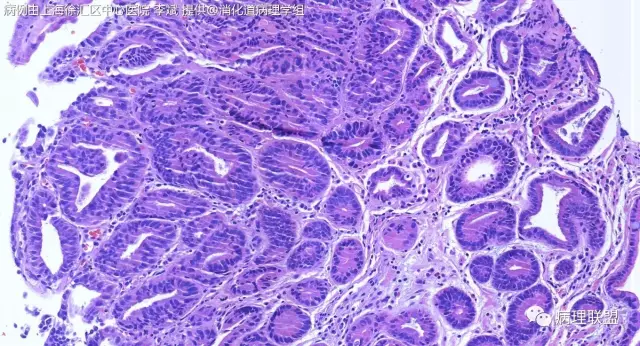

F-56 胃窦粘膜活检(低级别 vs 高级别)

女,56岁,胃窦粘膜活检(病例由上海徐汇区中心医院 李斌 提供,致谢!)

@李斌,高级别,腺体结构乱复杂,核异型性大,极向乱

@左淑英 子宫内膜受激素周期影响,腺体结构和上皮变化比较大,消化道受损伤、炎症等影响比较大,同样要看结构、看细胞,但标准确实不大一样。虽然具体病例需要具体分析,但我感觉在胃肠道,对于判断时感觉模棱两可的病例,表面成熟现象是区分反应性增生和低级别异型时可重复性相对比较好的指标;核极向是区分高低级别异型增生时可重复性相对比较好的指标。供参考